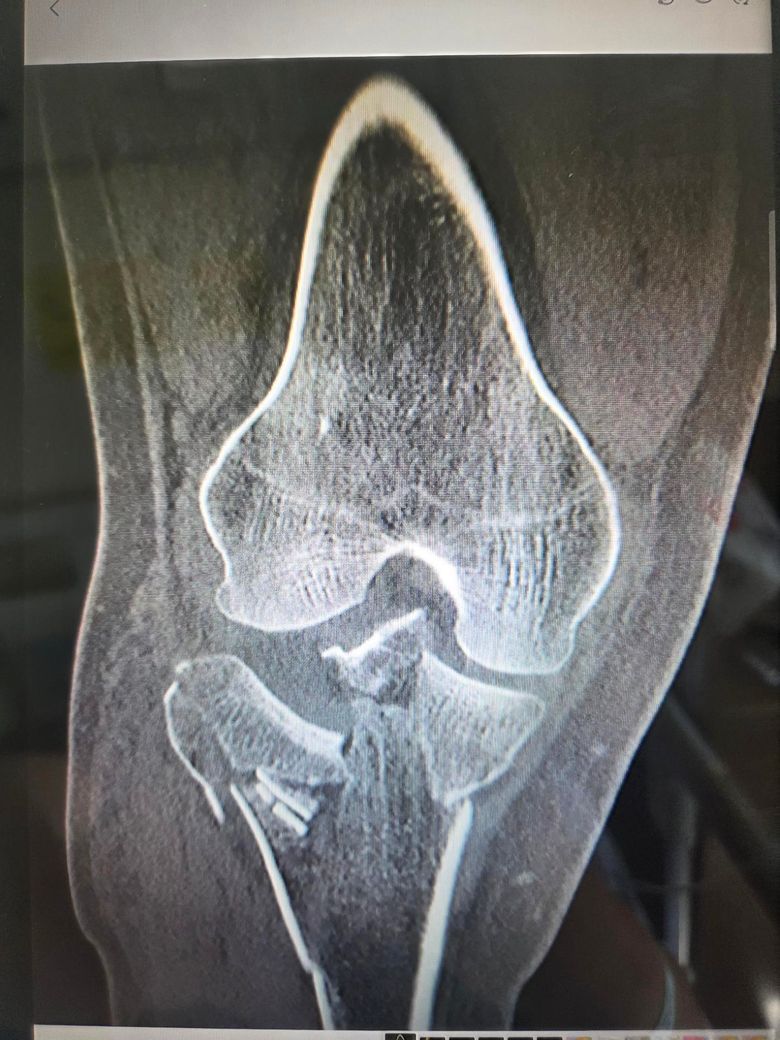

MRI가 아닌 X-ray 영상이지만, 분쇄 골절 정도가 심한 것으로 보이며 아마 무릎 내의 인대들도 손상이 있을 것으로 추측되는 상태네요. 주치의선생님이 말씀하신 것 처럼 예후가 좋지 않을 수도 있지만, 나이가 젊으시기 때문에 생각보다 많이 좋아지는 경우도 실제로 있습니다. 장애진단은 최소 6개월 지난 후에 그때 근력이나 가동범위 상태에 따라 지체장애중에 어떤 장애로 나갈지 판단하기 때문에, 일단 너무 걱정하지마시고 수술 후 재활치료 잘 받아보세요.

관절면을 심하게 침범한 골절이라 관절의 구축이 생길 수 있다는 이야기를 해주신겁니다.